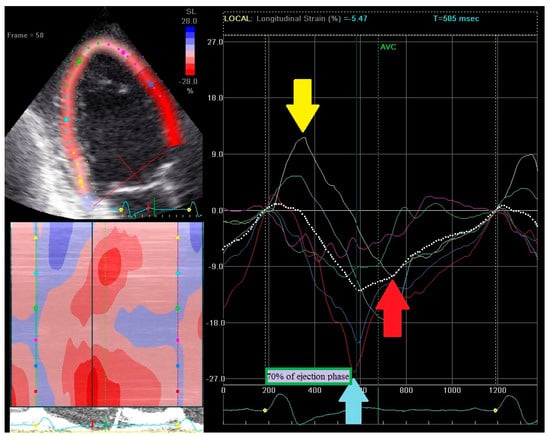

2.3. Echocardiography—Strain Pattern Analysis

- (1)

- Early contraction of at least one basal or midventricular segment in septal or anteroseptal wall and early stretching in at least one basal or midventricular segment in the opposing wall,

- (2)

- the early peak contraction does not exceed 70% of the ejection phase,

- (3)

- the early stretching wall shows a peak contraction after aortic valve closure.